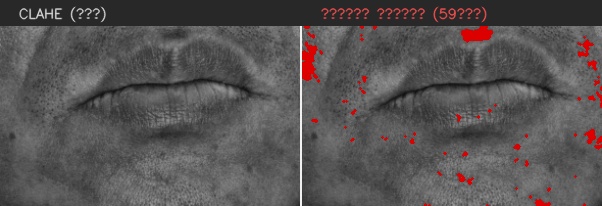

이마

유효 주름 수 4개 · 주 방향 가로

상위 깊이(평균 상위3) 0.320 mm

| # | 길이(mm) | 깊이(mm) | 유효 판정 근거 |

|---|---|---|---|

| 1 | 8.63 | 0.110 | 대표 깊이 0.110 mm가 이 부위 최소 깊이 0.100 mm 이상이고, 유효 길이 8.63 mm가 최소 길이 5.00 mm 이상이어서 노이즈·미세선과 구분되어 유효 주름으로 집계되었습니다. |

| 2 | 10.47 | 0.161 | 대표 깊이 0.161 mm가 이 부위 최소 깊이 0.100 mm 이상이고, 유효 길이 10.47 mm가 최소 길이 5.00 mm 이상이어서 노이즈·미세선과 구분되어 유효 주름으로 집계되었습니다. |

| 3 | 5.76 | 0.322 | 대표 깊이 0.322 mm가 이 부위 최소 깊이 0.100 mm 이상이고, 유효 길이 5.76 mm가 최소 길이 5.00 mm 이상이어서 노이즈·미세선과 구분되어 유효 주름으로 집계되었습니다. |

| 4 | 14.61 | 0.477 | 대표 깊이 0.477 mm가 이 부위 최소 깊이 0.100 mm 이상이고, 유효 길이 14.61 mm가 최소 길이 5.00 mm 이상이어서 노이즈·미세선과 구분되어 유효 주름으로 집계되었습니다. |